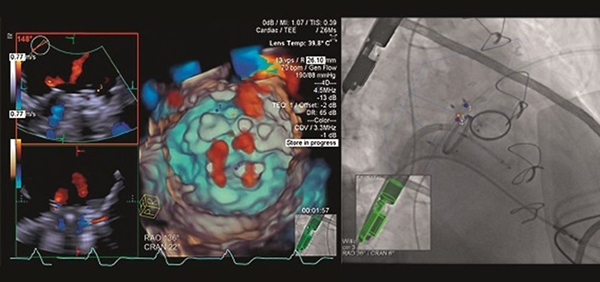

特長<6>

安全で確実な手技に貢献する「TrueFusion」

Siemens Healthineersの血管撮影装置画像と,超音波画像診断装置から得られた情報を重ね合わせて表示することが可能です。血管撮影装置だけでは確認できない心臓の解剖学的情報を,超音波画像診断装置から得られた情報をもとに付加することで,安全で確実な手技に貢献します。また,手技時間の短縮や造影剤使用量・被曝線量の低減なども期待できます。